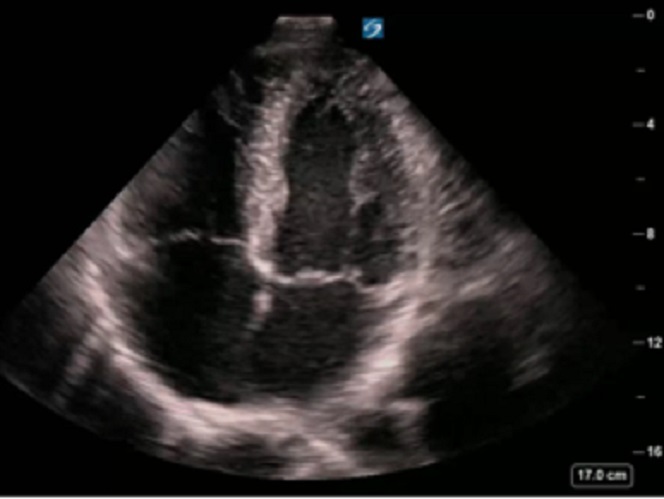

RUSH 右心劳损心尖视图图像